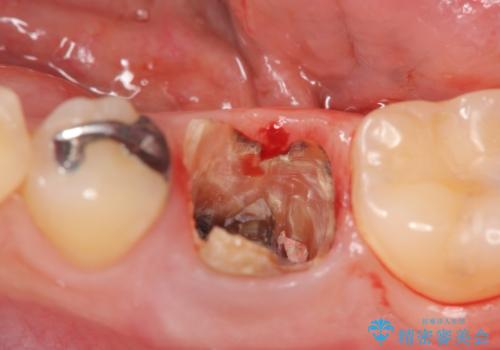

銀歯を除去して見ると内部で虫歯が再発し、歯の辺縁は破折し保存が難しく抜歯をしなければいけない状態でした。

抜歯後ブリッジとインプラント治療を検討・相談し、より周囲の歯を削らずに済むインプラント治療を希望されたのでインプラントによる機能回復を計画します。

銀歯に限らず神経を除去する根管治療を行なった歯は、痛みが出ないまま虫歯が進行していることもしばしばみられます。

外から見ても状況は全くわからないことが多いため、X線による定期的な検査が重要です。